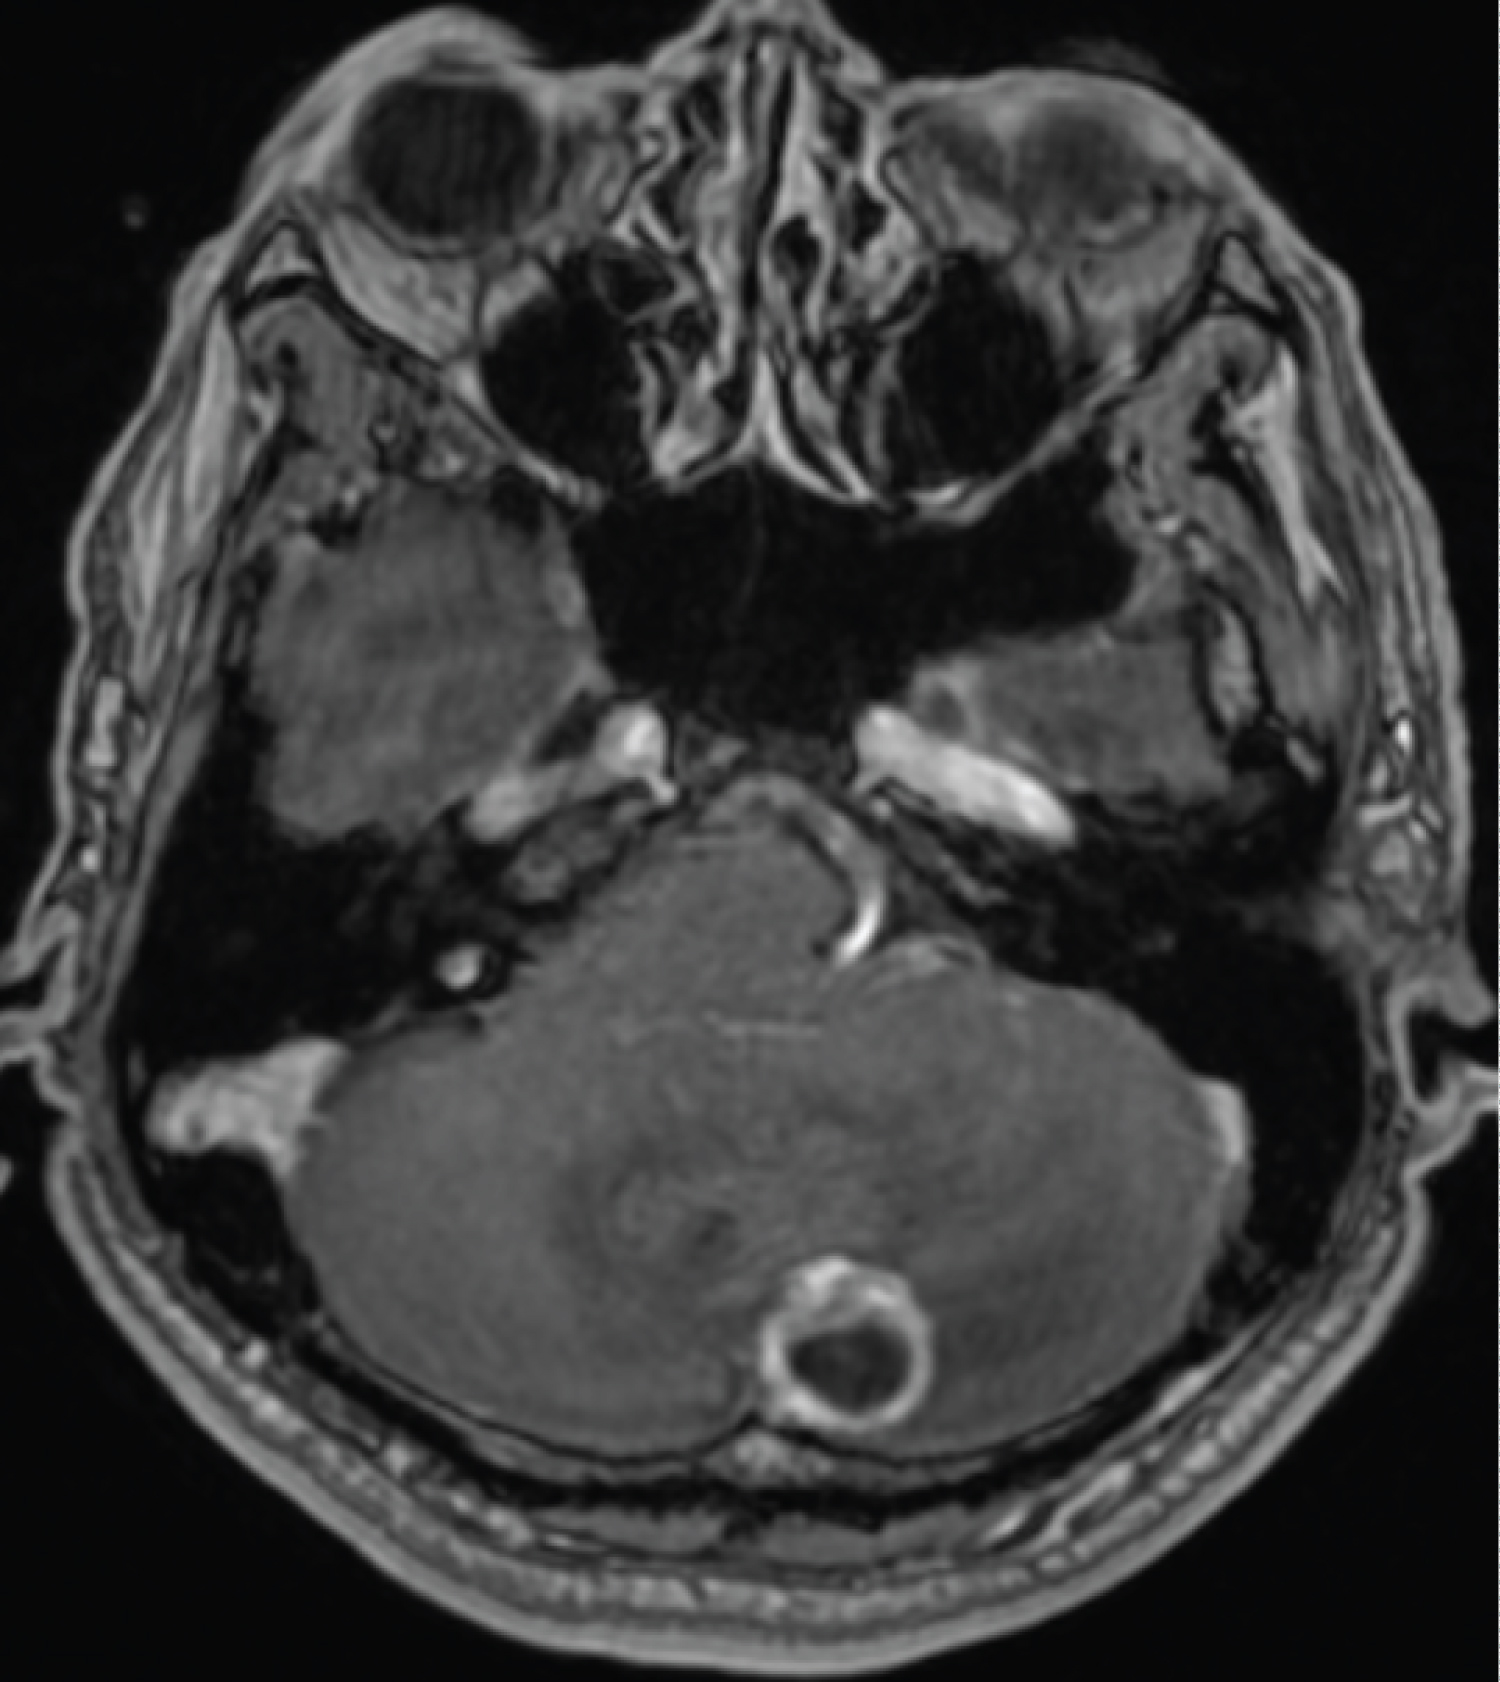

Figure 2: Pre-operative MRI brain with contrast which showed ring enhancing left cerebellar cystic lesion with mural nodule which is typical of hemangioblastoma. View Figure 2